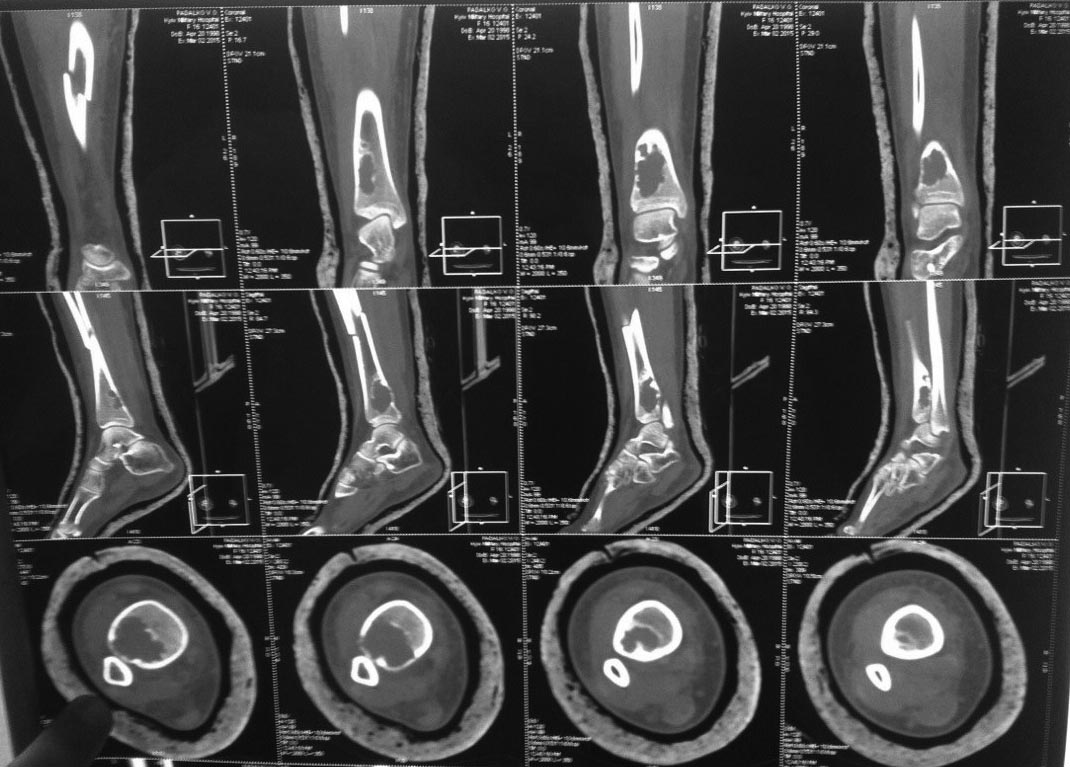

КТ

Уважаемый Анатолий.На данный момент снимок без гипса отсутствует (пропал у родителей после первичной амбулаторной консультации. М.берцовая-целая.Сегодня будет КТ-направили для оценки патологической перестройки очага. Спасибо.

Добавляю информацию и пару встречных вопрссов: обычно в таком формате рентгенологически либо аневризмальная костная киста,либо фиброзная дисплазия. Мнения интересные, по поводу биопсии согласен, но вышеуказаные патологии можно определить визуально при биопсии, а гистологически - подтвердить.